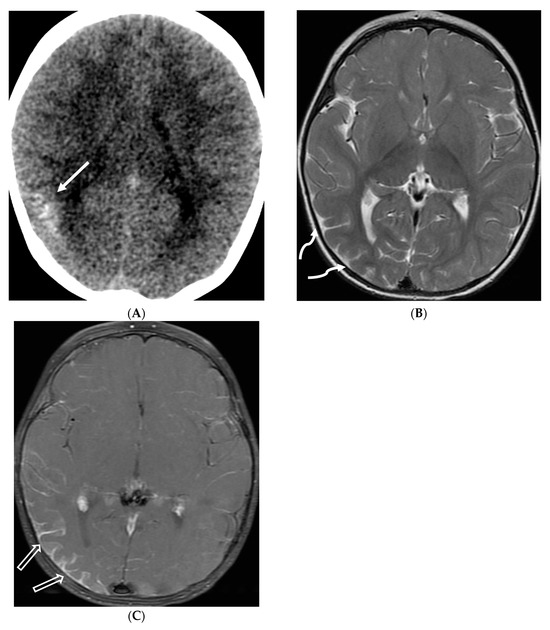

MRI is the primary imaging modality for detecting PRES [13,16]. T2-weighted and FLAIR images show hyperintense foci in the posterior parietal and occipital lobes, but also frequently involving other regions, including the frontal and inferior temporal lobes and cerebellum [124]. Few tiny to small foci of diffusion restriction may also occur. As per Agarwal et al., leptomeningeal FLAIR signal was seen in about one third of the patients with post contrast enhancement (leptomeningeal +/− cortical) in about 25% of the total population. Majority of these were isolated and had no vasogenic edema [122]. In addition, increased gadolinium dose and delayed imaging increase the incidence of LME (Figure 24) [125].

Figure 24.

Axial FLAIR (A), post contrast axial T1 (B,C) and coronal T2 (D): 6 year 9-month-old male with sickle cell disease presented with altered mental status, seizure and hypertension. Multiple areas of T2/FLAIR signal hyperintensities are seen in a relatively symmetric distribution involving the bilateral occipital, posterior parietal, high frontal and posterior temporal lobes (arrows). Multiple areas of LME are demonstrated in the involved regions (curved arrows). These findings are characteristic of posterior reversible encephalopathy syndrome (PRES). Areas of encephalomalacia and gliosis involving the deep white matter of bilateral frontal lobes (dashed arrow) and a small area of old cortical infarct involving the right frontal lobe (open arrow), secondary to small vessel disease in a patient with sickle cell disease.